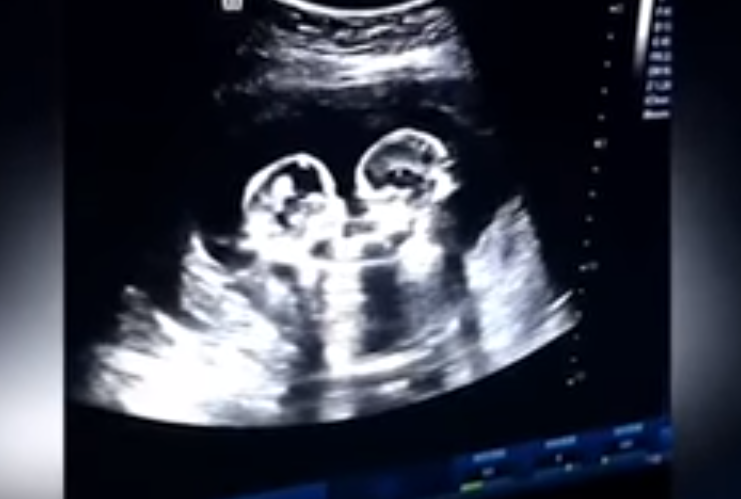

En Yinchuan, China, un caso sorprendió a la comunidad médica. Unas gemelas que compartían saco amniótico y placenta se encontraban cara a cara y parecían golpearse entre sí. Cuatro meses después nacieron sanas, pero pudo ser un caso complicado, porque se encontraban creciendo en el mismo espacio.

En el caso de estas gemelas, fue un caso monocorial monoamniótico donde dos fetos se alimentan de la misma placenta y comparten el saco del líquido amniótico. No comparten el mismo cordón umbilical y en el 75% de los casos suelen ser del género femenino. El diagnóstico se realiza mediante ecografía, durante la semana 9 y 10 de gestación.